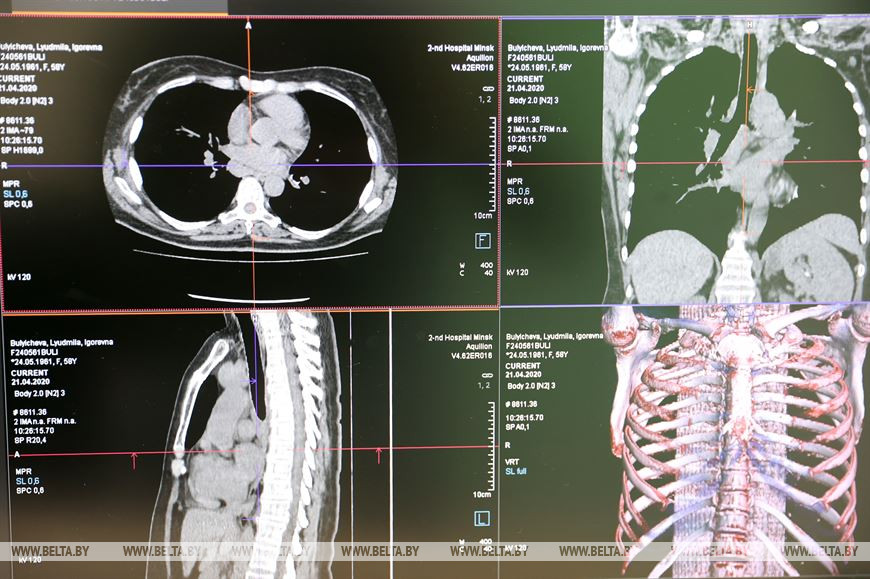

Рентгеновский компьютерный томограф Siemens на 64 среза поставлен по линии Минздрава. Оборудование приобретено за счет займа Международного банка реконструкции и развития в целях борьбы с COVID-19. Это один из 25 КТ-аппаратов, закупленных для Беларуси.

Аппарат делает 64 среза. Благодаря этому можно диагностировать заболевания на более ранних стадиях. Особенно это важно для выявления онкологических опухолей, нарушений системы кровообращения, поражений легких.

"Это второй рентгеновский компьютерный томограф в больнице. Существующий КТ эксплуатируется с 2007 года, он технически устарел. Для установки нового оборудования провели реконструкцию помещений. Современный КТ позволяет проводить порядка 40 исследований в смену. Время на их проведение значительно сократится. Плюс есть набор программ, которые позволят применять различные методики, чтобы более качественно выявлять заболевания", - уточнил заведующий рентгеновским отделением, в состав которого входит кабинет КТ, Сергей Пунько.